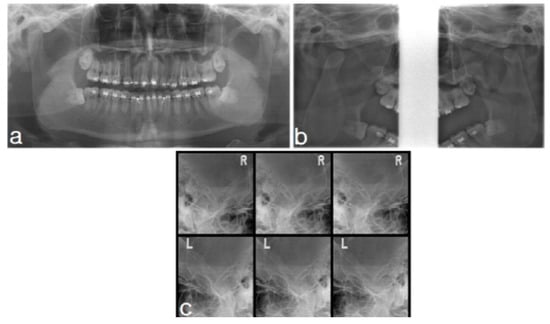

2.1.2. Imaging

2.2.2. Imaging